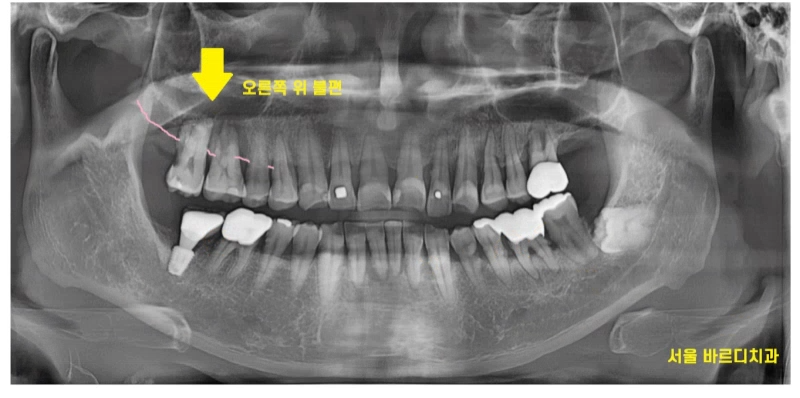

전반적으로 잇몸이 많이 내려가신 상황이었는데요.

불편을 호소하신 오른쪽 치아를 보니

겉으로 보기에는 닳은 치아가 있긴 했지만

환자분 연령을 생각하면 크게 문제가 되는것은 아니었습니다.

잇몸뼈가 많이 내려가

치아를 움직여봤는데요.

어금니가 들썩 들썩

위 아래, 좌우로 움직였습니다.

치아가 뽑힐정도로 말이죠.

x-ray상에서 치석이 보일정도로

치석도 많고 잇몸관리가 안되고 계셨어요.

오른쪽 어금니 시림으로 내원하셨지만

다른 치아들도 상태가 영 .. 좋지 않았죠.